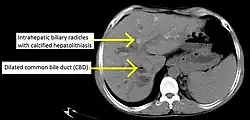

CT scan findings in a case of primary sclerosing cholangitis